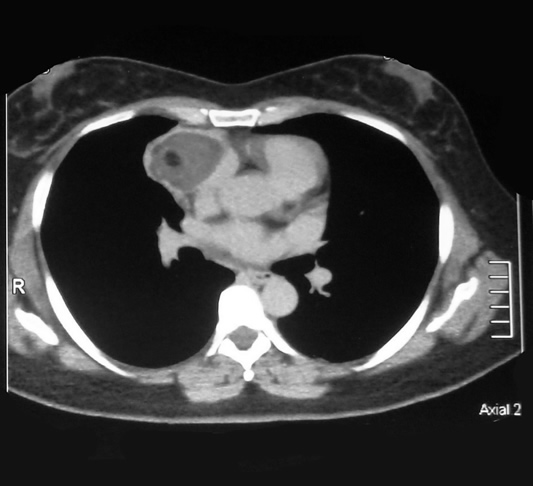

Corte Axial en hileo pulmonar

La lesión con forma de pera, encapsulada y densidad heterogénea, su parte mas amplia para cardiaca derecha ocupa el ángulo pleuropericardico anterior y el cuello posterior de la lesión en relación con el seno de la arteria pulmonar y la vena cava superior.

El seno cardiofrenico esta libre y sin derrame pleural.

Corte Axial debajo de los hileos

Un corte axial mas bajo al precedente: la lesión en su mayor diámetro, en relación adosada con la aurícula derecha y el cono aórtico, parece comprimir el parenquima pulmonar ocasionando atelectasia laminar.